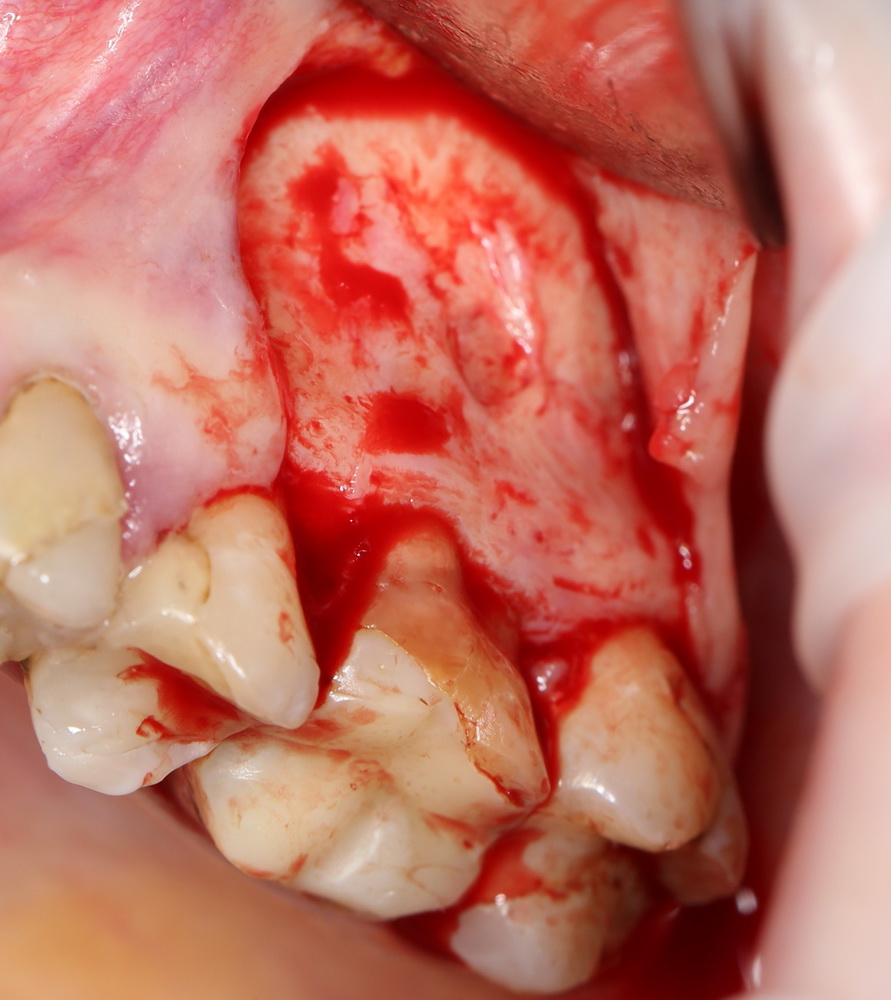

Если в зоне операции присутствует зуб, то разрез проводится по зубодесневой борозде (рис 18, 19):

Рисунок 18, 19. Схема разреза при наличии зуба в области операции

как и при проведении операции синуслифтинга одномоментно с удалением зуба (рис 20):

Рисунок 20. Схема разреза при сочетании синуслифтинга с удалением зуба

Необходимым условием для проведения этого вмешательства является стадия ремиссии воспалительного процесса в области удаляемого зуба, отсутствие или небольшие размеры очагов хронического воспаления в прикорневой зоне (рис 49, 50, 51):

Рисунок 49, 50, 51. Проведение операции синуслифтинга одномоментно с удалением зуба: слева – скелетирование стенки верхней челюсти, подготовка к удалению зуба, в центре – лунка удаленного зуба (виден небольшой очаг деструкции костной ткани вследствие хронического периодонтита), справа – заполнение субантральной полости спейсером.